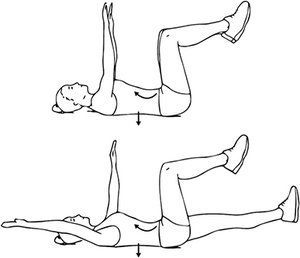

Abdominal hollowing is another core stabilization tool that follows a progression, just as any other stabilization exercise. For example, in the supine position, a common progression would be:

- Dead bug position

- Dead bug position (leg motion only)

- Dead bug position (arm motion only)

- Dead bug position with both arm and leg motion